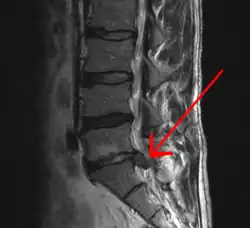

МРТ-изображение межпозвонковой грыжи между сегментом L5 поясничного отдела и крестцом.

Методом выбора диагностики грыж межпозвонковых дисков в настоящее время является магнитно-резонансная томография (МРТ) или мультиспиральная компьютерная томография (МСКТ). При необходимости проводится неинвазивная МР-миелография или инвазивная КТ-миелография.